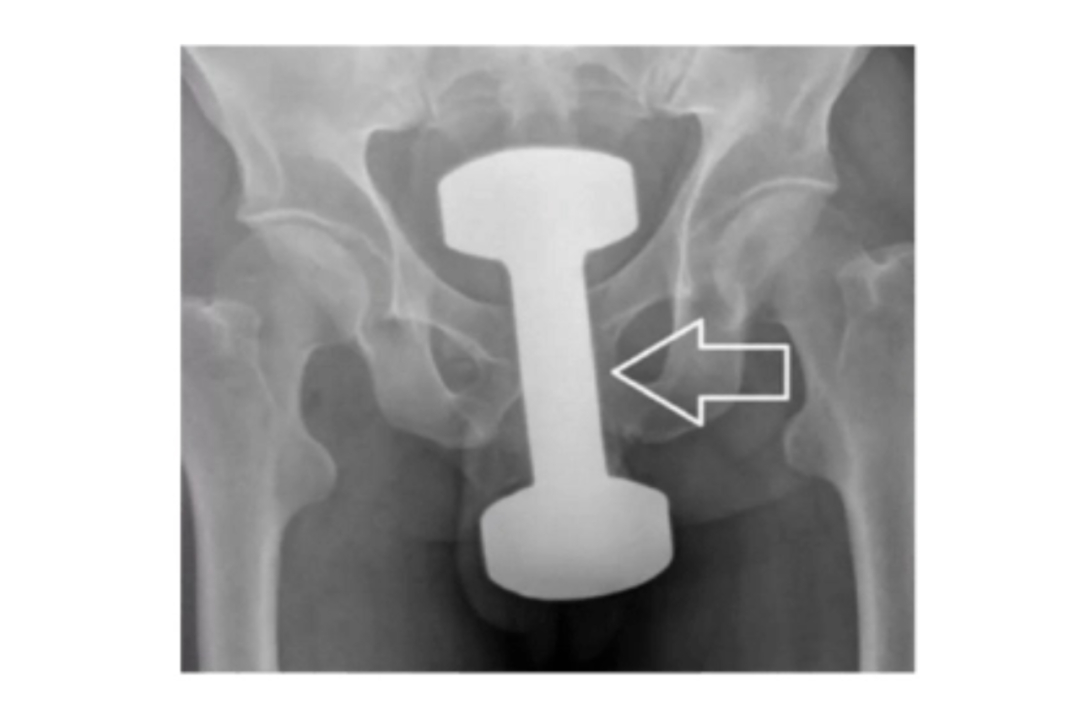

【#深圳14岁男孩网购假阳具塞入肛门#!“不小心整个滑进去”,医生提醒】#14岁男孩因好奇往肛门塞假阳具##肛门就像哆啦A梦的百宝袋#近日,深圳市松岗人民医院分享了一个案例:一名14岁的男孩因好奇心网购假阳具,并塞入了肛门,后来不小心整个滑了进去,肚子变得涨涨的,吃不下东西,也拉不出来。因就医及时,发生当晚就取出了,所以肛门、肠道未受到伤害。

对此,医生提醒:肛门内塞异物很难自然排出,多数需医生取出。长时间不取可能导致肠穿孔、肠梗阻等严重后果,越晚就医风险越大。同时医生建议家长:不要责怪孩子,否则下次遇到问题可能不敢求助;与其让孩子偷偷试错,不如大方引导;此外可带孩子接种HPV疫苗。(来源:综合深圳市松岗人民医院)